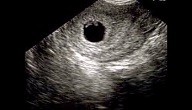

النبض في بداية الشهر الثاني يمكن ملاحظته من خلال انقباض وانبساط قلب الجنين داخل كيس الحمل في الأسبوع الخامس أو السادس وهناك من يخضعن إلى تصوير مهبلي وفحص سونار داخلي لسماع نبض الجنين الذي يكون ضعيف في هذه الفترة ويصعب سماعه، ثم يتم سماعه بوضوح من خلال عمل سونار خارجي في نهاية الشهر الثاني في الأسبوع السابع والثامن وتبدأ الأم بالشعور بالنبض بنفسها في الشهر الرابع من وقت لآخر بوضع يدها على منطقة أسفل البطن، وإن لم تشعري بالنبض لفترات طويلة متقطعة يجب حينها استشارة الطبيب للتأكد من سلامة الجنين والاطمئنان لعدم وجود مشكلة مع العلم أنه من الشهر الرابع يمكنك متابعة نبض جنينك باستمرار ومع بداية الشهر السادس ودخول الشهر السابع يمكنك لمس تحركاته بشكل شبه مستمر وأي خلل في هذه الأمور يُرجى متابعة طبيبك فورًا.

عادة يبدأ قلب الجنين بالتكوّن بعد الأسبوع الخامس من الحمل أي بعد مرور الشهر الأول، ويبلغ طول الجنين حوالي 1.25 مم، وتبدأ بعض الخلايا بالتشكيل. وفي نهاية الأسبوع الخامس، يبدأ الجنين يتخذ شكل معين ويبدأ الجزء العلوي من الدماغ بالبروز والظهور بشكل واضح. كذلك تقع حبة صغيرة في منتصف الجنين لتتطور وتصبح قلب الجنين فيما بعد. هنا يبدأ ظهور النبض، أي في الفترة ما بين الأسبوع السادس والأسبوع السابع من الحمل، ويمكن للطبيب معرفة ذلك عن طريق استخدام جهاز السونار فقط. ومع تقدم مراحل الحمل وتطوره، يمكن للطبيب سماع نبض الجنين بالسماعة الخاصة به، أي بعد مرور الاسبوع العشرين من الحمل.